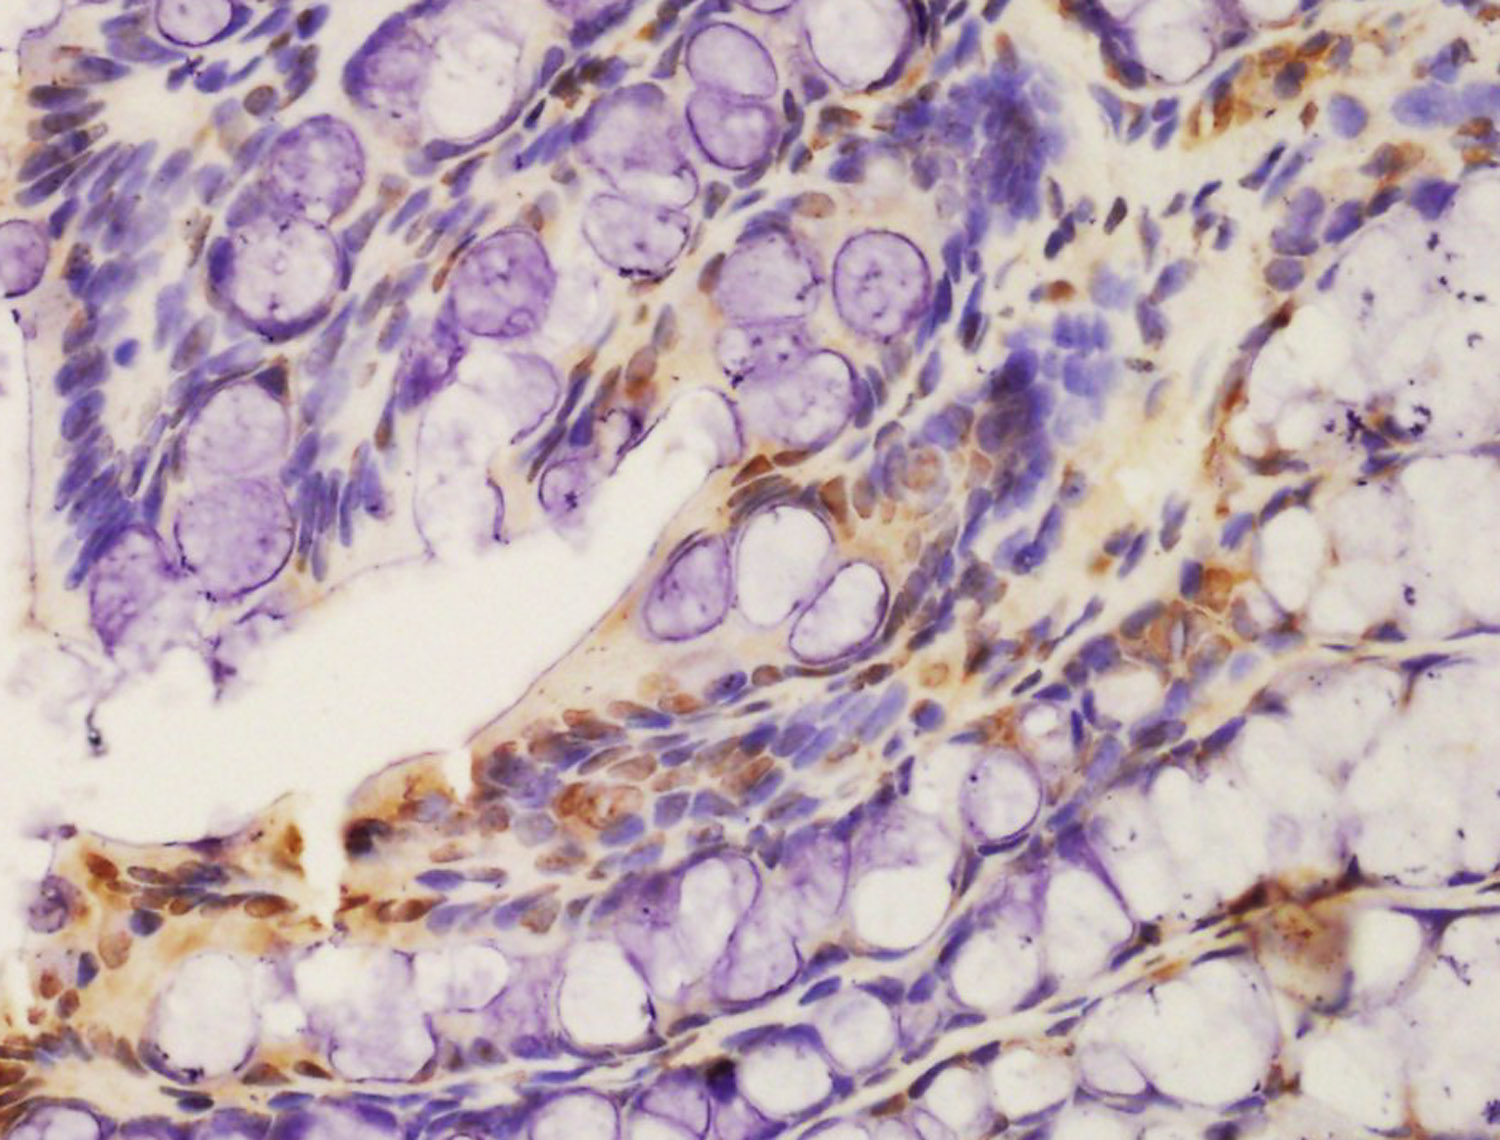

Tissue/cell: rat colon tissue; 4% Paraformaldehyde-fixed and paraffin-embedded; Antigen retrieval: citrate buffer ( 0.01M, pH 6.0 ), Boiling bathing for 15min; Block endogenous peroxidase by 3% Hydrogen peroxide for 30min; Blocking buffer (normal goat serum,C-0005) at 37℃ for 20 min; Incubation: Anti-phospho-CSK(Ser364) Polyclonal Antibody, Unconjugated(bs-12942R) 1:200, overnight at 4°C, followed by conjugation to the secondary antibody(SP-0023) and DAB(C-0010) staining